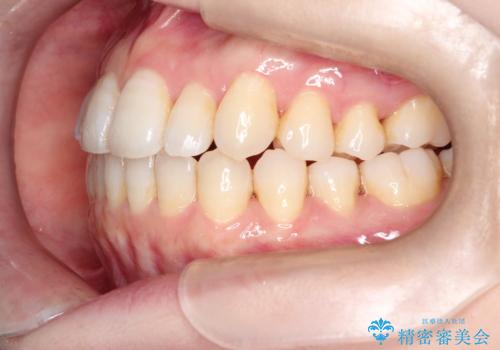

インビザラインで八重歯の矯正

- 八重歯を治したいとのことで、来院されました。

インビザラインにて、上顎の歯と歯の間をわずかに削り、並べる計画としました。

使用時間を守っていただけたので、比較的スムーズに矯正を終了することができました。